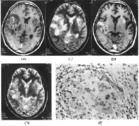

腦膿腫綜合症多是病原菌經血行播散至腦,往往見於體質衰弱或長期套用皮質類固醇激素的患者,此種病人予後不佳。

(2)組織病理檢查:只侵犯表皮、真皮,不侵犯皮下組織。表皮呈假上皮瘤樣增生,表皮、真皮內有小膿腫。在小膿腫和異型多核巨細胞內可見不同形態的棕黃色硬殼細胞(厚壁抱子)。

1911年Pedroso首次報導CM後,1973年Ajello等根據病原學、臨床表現將CM分為PHM及CBM兩個病種,至今已得到認可。暗色孢科真菌為一類條件致病菌,生長在潮濕的土壤、木材、麥稈及雜草中。PHM由枝孢霉(cladosporium)、外瓶霉(exophiala)、瓶霉(phialophora)、交鏈孢收(alternaria)等引起,文獻報導導致中樞神經系統感染者多為斑(氏)枝孢霉(cladosporium trichoides)及裴德羅索著色霉(hormodendrum pedrosi)。組織病理為棕色分隔的菌絲。臨床表現主要分為兩種類型,其中一類為皮下組織暗色絲孢霉病,常為單一的皮下或肌肉的膿腫,有時為皮下囊腫。另一類為系統性暗色絲孢霉病,為黴菌血行播散,引起多臟器系統性感染,主要是腦部感染。CBM由裴(氏)瓶霉(fonsecaeapedrosoi)、疣狀瓶霉(phialophoraverrucosa)、緊密瓶霉(fonsecaeacompacta)、卡(氏)分枝孢子菌(cladosporiumcarrionii)及嗜脂著色霉(rhinocladiellacerophilum)5種暗色孢科真菌引起。患者多見於農民、伐木工人,常因皮膚損傷後感染,局部出現丘疹、結節、潰瘍或結痂,常數年或數10年不愈,組織病理學為棕色厚壁孢子。